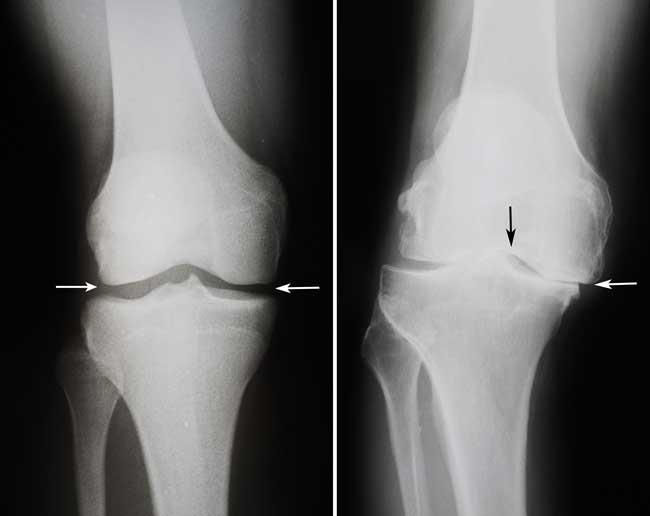

Radiografias. As imagens obtidas com esta técnica ajudam a determinar a extensão dos danos e as deformidades no joelho.